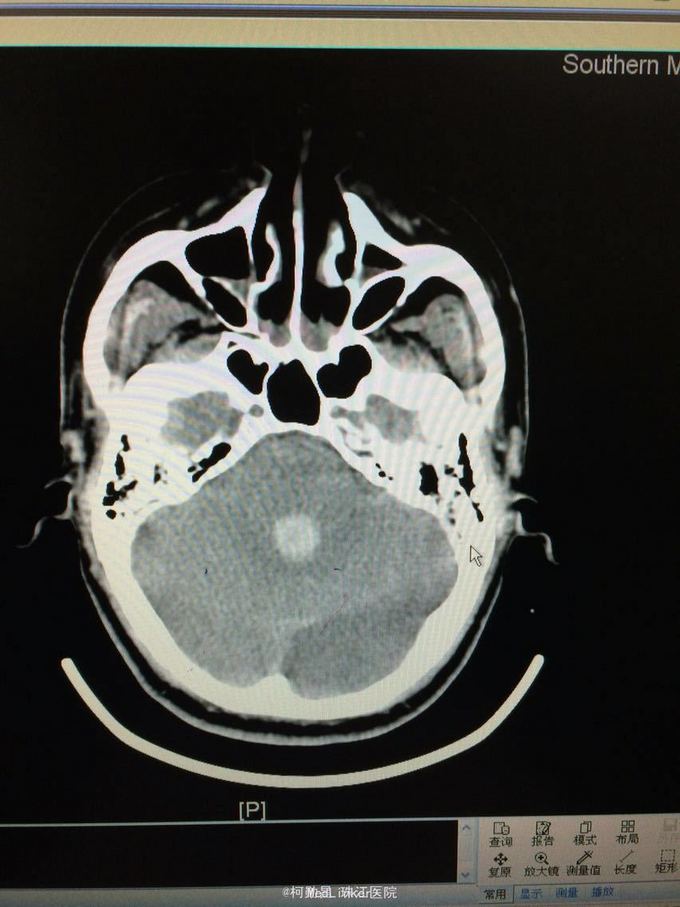

主诉:突发意识障碍4小时 病史:患者57岁男性,入院前一天晚上突发意识不清,伴呕吐胃内容物多次,无肢体抽搐等,随即由家人呼叫120送至我院,急诊行头颅CT提示左侧基底节区出血破入脑室。既往高血压病史10多年

查体:神志不清,双侧瞳孔散大,对光反射消失,四肢肌张力正常,肌力无法检查 辅助检查:头颅CT提示左侧基底节区出血破入脑室

诊断:左侧基底节区出血并破入脑室 处理:急诊行侧脑室钻孔外引流术,术后并予积极抢救,最终抢救无效死亡